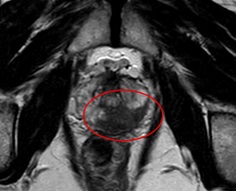

前立腺MRI

赤丸の部分が、がん

当センターの前立腺MRI検査では、さまざまな断面画像に加え、MRS(MRスペクトロスコピー)という特殊な方法を用いて検査を行っています。

「MRS」は体内の代謝物を検出する技術であり、前立腺ではクエン酸・コリンという2種の代謝物を測定することにより、がんの検出能向上や悪性度の評価に有用と言われています(正常ではクエン酸が豊富、がんではクエン酸が減少しコリンが上昇する)。しかし直腸ガスや生検後の出血の影響を鋭敏に受けやすいので、さまざまな検討を行い、その結果ルーチン検査として取り入れることに成功しました。